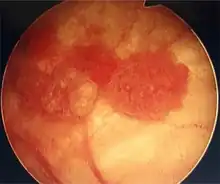

Cystoscopy: multiple papillary tumors on the right side of the posterior wall -